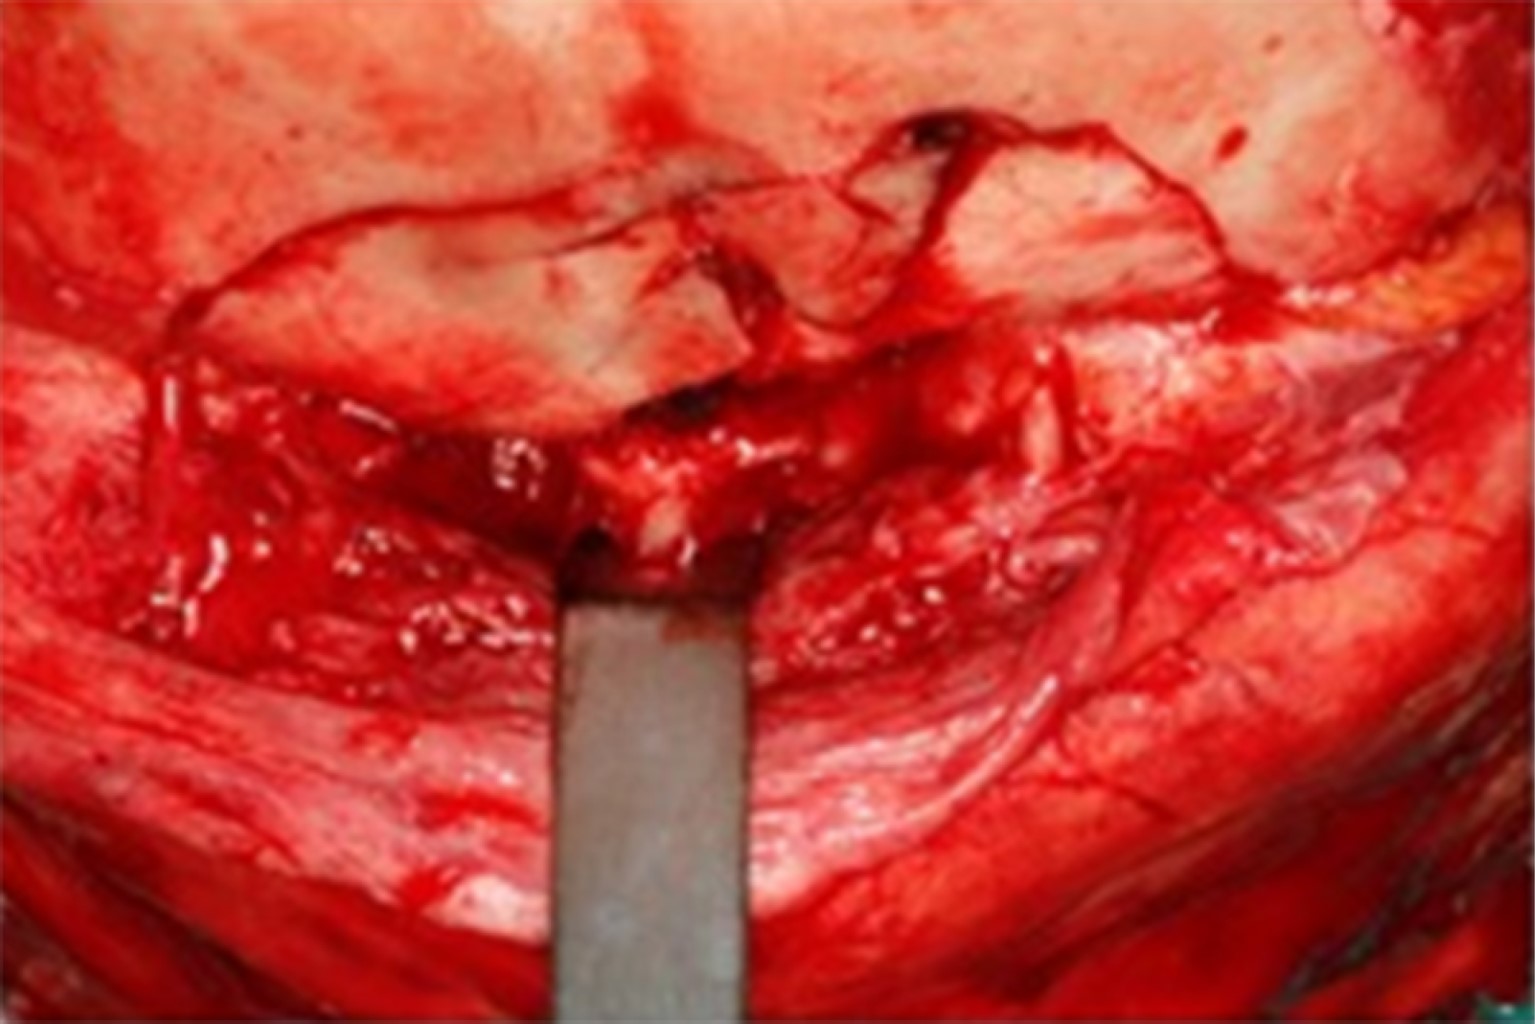

Bajo anestesia general, el paciente fue intervenido cinco días después del traumatismo para la reducción y fijación de las fracturas realizando un acceso bicoronal (Figura 1), infraciliar bilateral, sutura frontozigomática del lado izquierdo y acceso intraoral de Caldwell-Luc en fondo del saco superior del lado derecho. Las fracturas orbitarias bilaterales se reconstruyeron con malla de titanio en el suelo, la pared medial y el techo orbitario; todas las fracturas se fijaron con placas y tornillos del sistema de 1.5 mm; se realizó una prueba de ducción forzada con pinzas Adson y la movilidad del globo terráqueo fue satisfactoria (Figura 2).

En la tomografía computarizada postoperatoria de la cara se puede observar la reconstrucción de las fracturas del seno frontal, del techo, de la pared medial y del suelo orbitario y sus respectivas fijaciones (Figuras 3 y 4).

Paciente en seguimiento ambulatorio durante tres años sin quejas, se mantuvo clínicamente sin evidencia de infección ni complicación grave como diplopía y enoftalmia, buena proyección del cigomático derecho, sin cambios oculares ni intercurrencias durante este periodo postoperatorio (Figura 4).